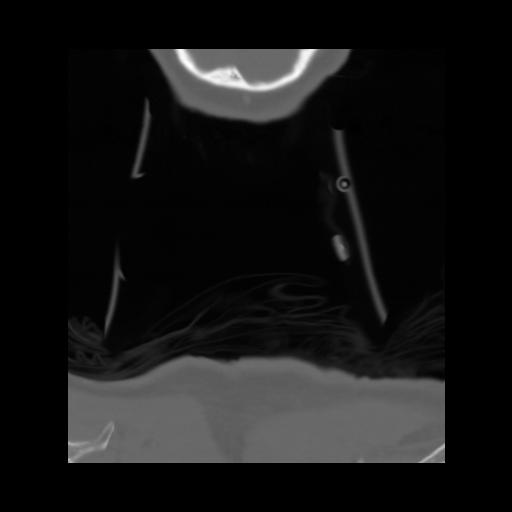

13 P.BLANDAS,,Coronal,2.000,P.BLANDAS,Coronal,